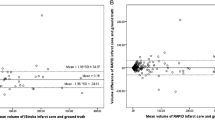

Scatter plots of hypoperfused tissue and ADC tissue volumes showed a good agreement between RAPID® and Olea Sphere® calculations (Fig. 2). However, the perfusion-diffusion mismatch determined by the two computer programs were significantly different (Fig. 3). The median volume of the perfusion-diffusion mismatch was 47.0 ml for RAPID® and 67.2 ml for Olea Sphere®, respectively (p < 0.05, z = − 6.32, r = 0.70). The median of volume of hypoperfused tissue was 91.0 ml for RAPID® and 102.2 ml for Olea Sphere®, respectively (p < 0.05, z = − 6.03, r = 0.67). ADC volume differences were determined as 30.0 ml for RAPID® and 23.9 ml for Olea Sphere® (p < 0.05, z = 3.77, r = 0.42), respectively (Fig. 3).

Bland-Altman analyses revealed that the hypoperfused tissue volume was largely estimated with Olea Sphere® compared with RAPID® (hypoperfused tissue mean = − 13.8 ml). ADC lesion volume was slightly largely estimated by RAPID® (ADC mean = 8.2 ml). Perfusion-diffusion mismatch volume was found to be larger when using Olea Sphere® (perfusion-diffusion mismatch mean = − 22.1 ml) (see Fig. 4). These results suggest the presence of a systematic bias when comparing both methods. However, no method over- or underestimated the evaluated mean volumes to a large extent.